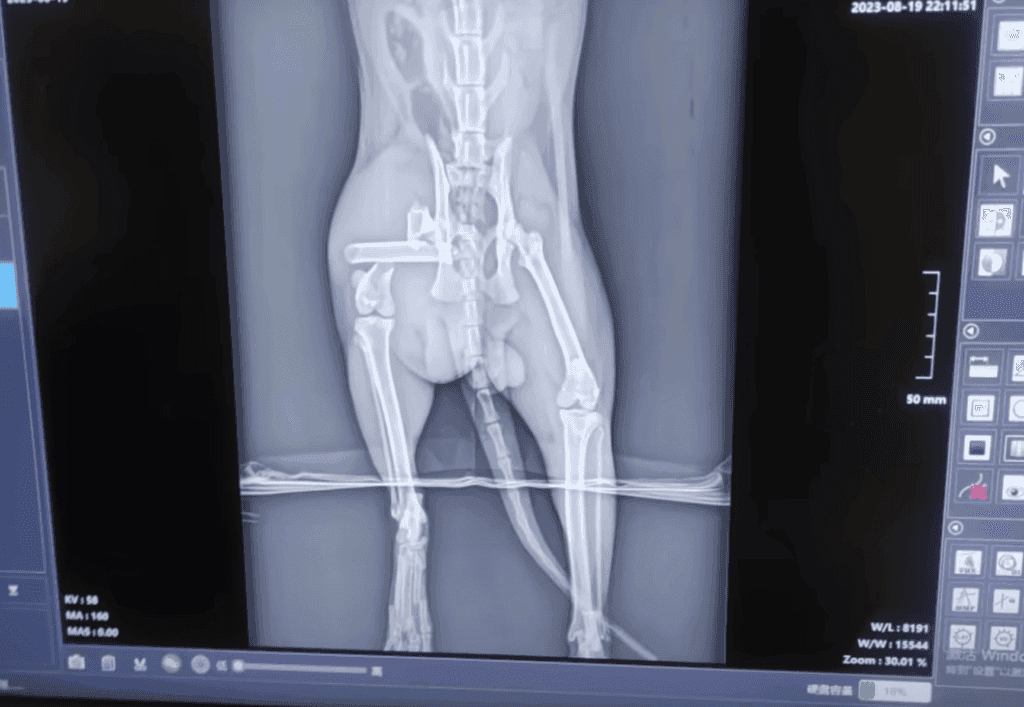

At the clinic, the situation took an even more horrifying turn. The cat wasn’t just injured, it was broken.

X-rays revealed multiple fractures in its legs, leaving the vet stunned at how much pain the tiny creature must have endured.

No wonder it kept twitching uncontrollably. To make things worse, its body had become a breeding ground for insects, with bugs burrowing into its open wounds.